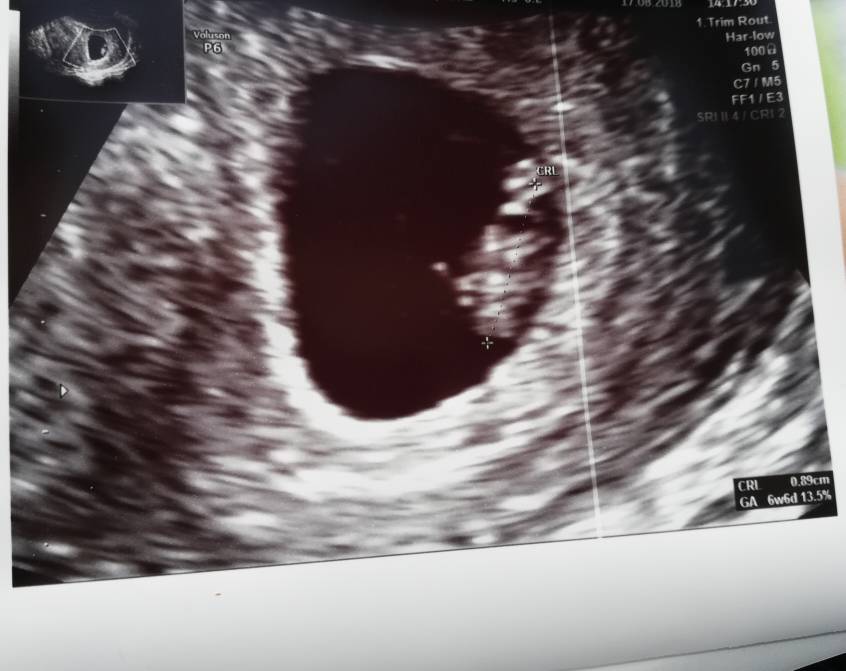

Hejka witam wszystkich, ja już po 1 wizycie jest pęcherzyk, 5w5d następna wizyta za 2,5 tyg i czekam na![]()

[emoji7] [emoji7] [emoji7] piękne widać mikro człowieka... który to tydzień u CiebieSvbsbxnxjjxnenu dnsjmzjdjejd

także po wizycie, serduszko pieknie bije. Z OM 7 tydzien 1 dzień. Termin na 4 kwietnia